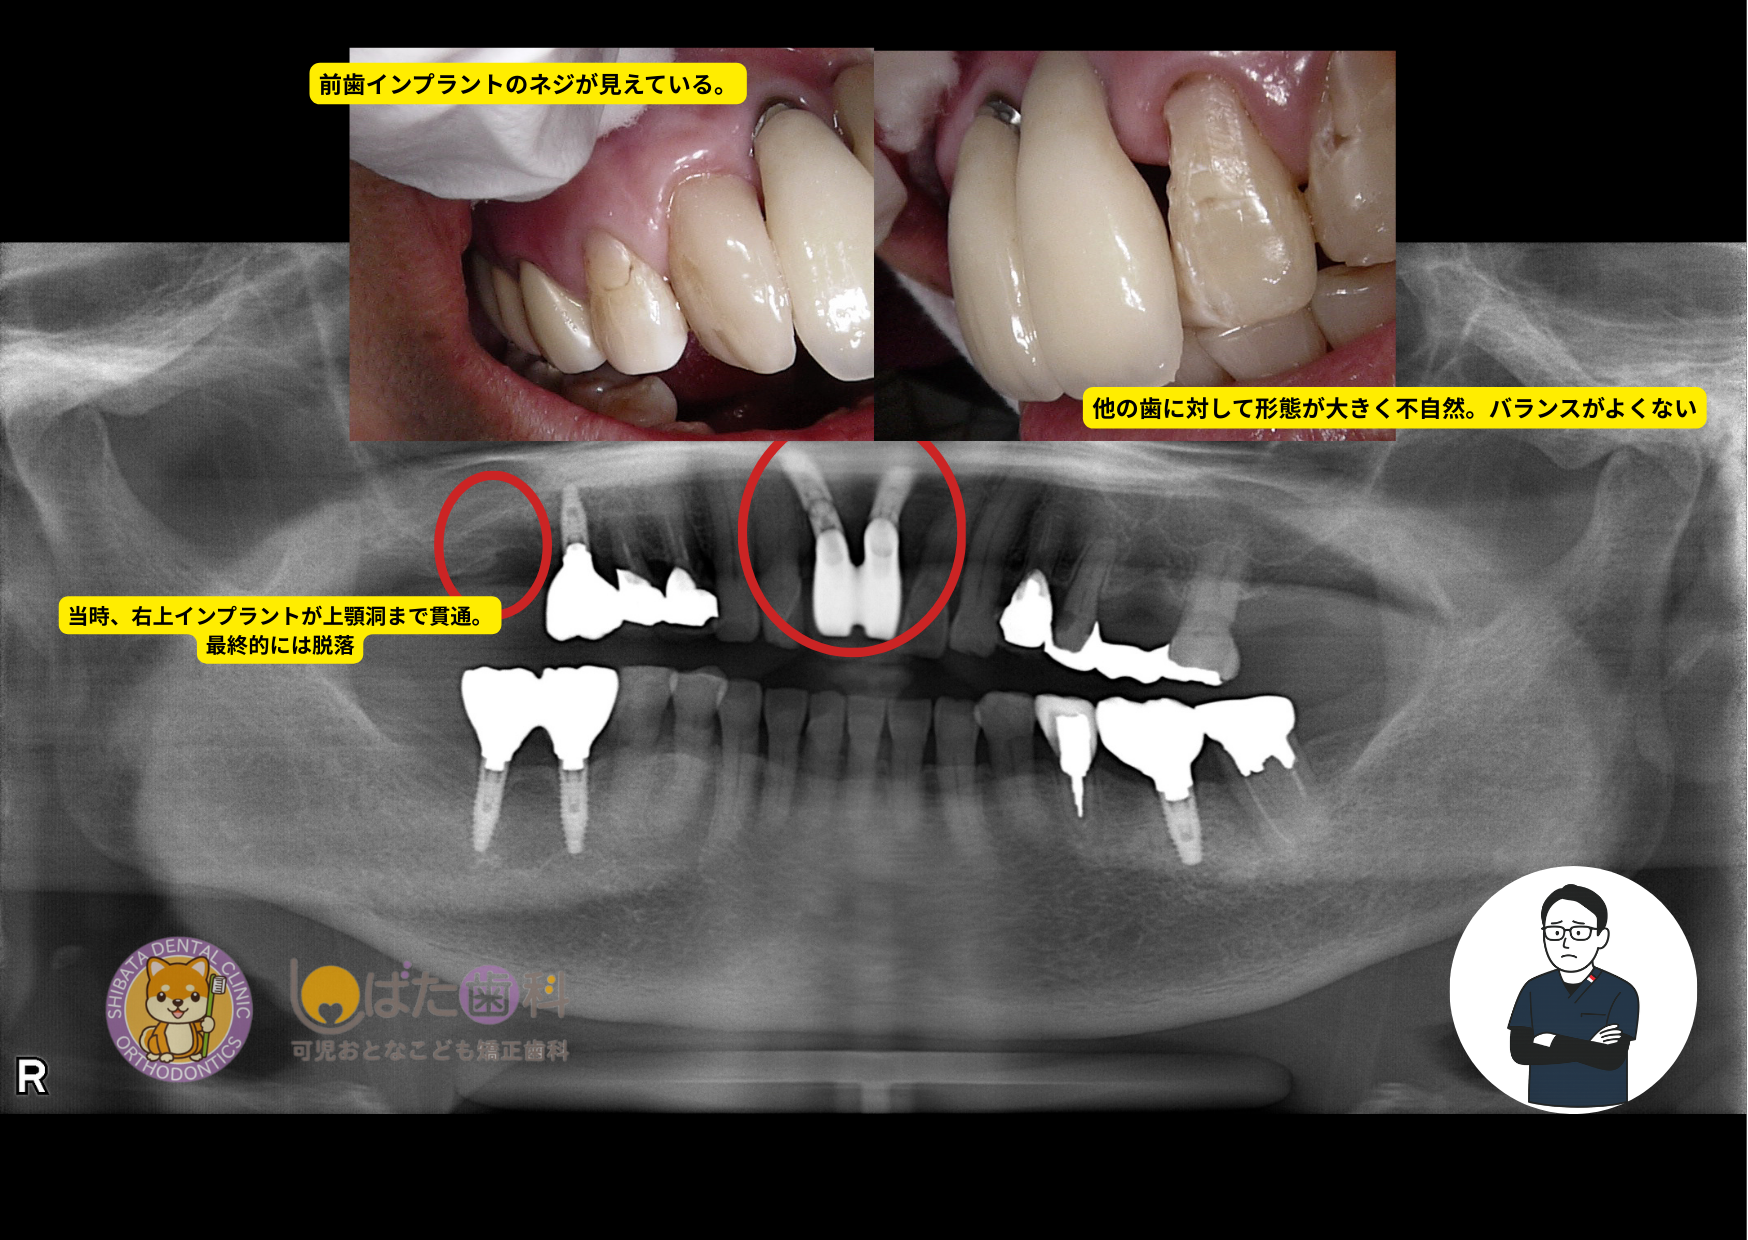

当時70代の女性。

「歯周病が気になる」とのことで当院に初めて来院されました。

詳しくお話を伺い、まずは精密検査を行うことに。

検査結果では、たしかに治療が必要な箇所も多くありましたが、今回のテーマにも関わる 「費用を優先して選んだ結果、トラブルを起こしてしまったインプラント」 が、ひとつ大きな問題として見つかりました。

具体的には、以下のような課題が確認できました。

過去の治療を評価する意図はなく、当時の状況にはさまざまな背景があったことと思います。ただ、今後の治療をより良い方向へ進めるためにも、現状の課題を共有させていただくことが重要だと考えています。

しかし 費用の安さを優先した結果、本来長期的に使用できるはずのインプラントが短期間で問題を生じ、再治療の費用や治療期間の負担が増えてしまう といった、いわゆる「負のループ」に陥ってしまうケースがあるのも事実です。

しかし 費用の安さを優先した結果、本来長期的に使用できるはずのインプラントが短期間で問題を生じ、再治療の費用や治療期間の負担が増えてしまう といった、いわゆる「負のループ」に陥ってしまうケースがあるのも事実です。